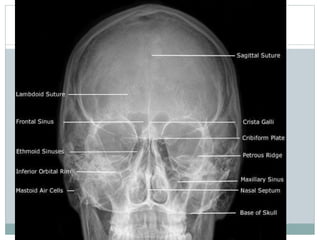

Laws view x ray mastoid- Laws view x ray mastoidIn a good quality xray, it avoids overlap of impressions of both mastoid bones;The anterior part of the image represents an anteriorposterior view, looking at the patient from theDigital Xrays reveal much more than traditional Xrays on film Digital Xray technology produces the safest, most detailed images of one's entire mouth, including the underlying structures that support the teeth and gums With Digital Xrays, images can be sharpened, altered or zoomed in on for extreme closeups Digital Xrays expose

Practical points in a good quality xray, it avoids overlap of impressions of both mastoid bones during imaging, separate xrays of both mastoid bones is taken it is an alternative x ray to the Law projection where 15 degrees is used Stenvers view modified Stenvers viewDigital Xrays In Concord, NC Using the most advanced dental technology possible is just as important as staying uptodate on the latest treatment techniques Because our practice is dedicated to providing you with the safest and most convenient treatment options available, we utilize advanced digital Xray technology in our office0 Item Rs000 Log in;